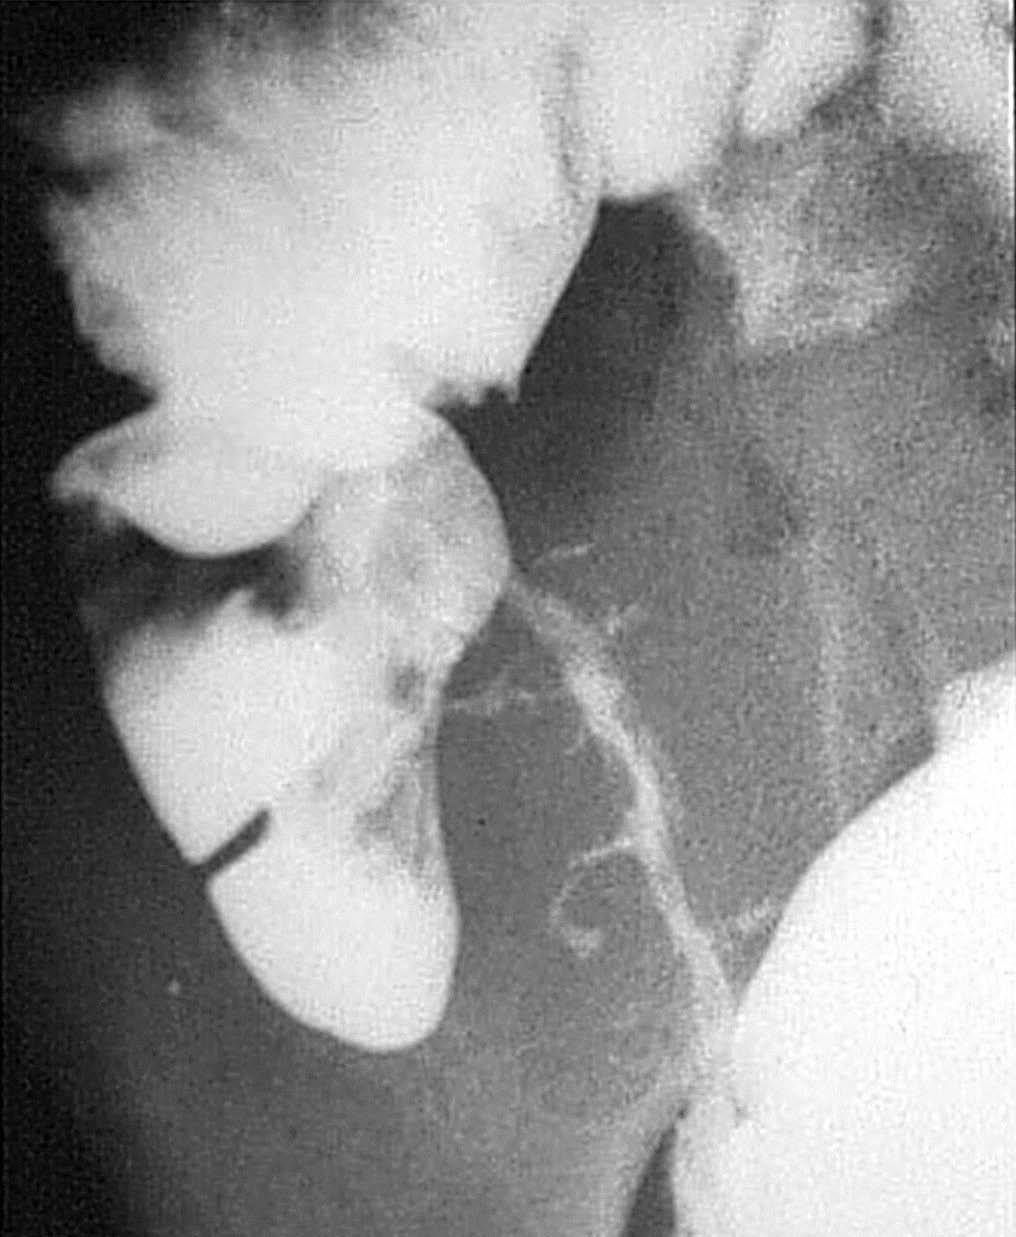

Para los pacientes con EC el riesgo de padecer una fístula durante su vida se sitúa entre el 20 y el 40%. En el caso de las fístulas perianales el riesgo es acumulativo y aumenta con el paso de los años: del 21% a los 10 años, al 26% después de los 20 años de enfermedad18. En el diagnóstico por imagen de las fístulas anorrectales la fistulografía está siendo reemplazada por la RM, que ha demostrado gran precisión a la hora de determinar y diferenciar los trayectos fistulosos y abscesos8,19,20. Las ventajas de la RM frente a la TC son la mayor resolución tisular en el estudio de partes blandas de la región pélvica y la mayor resolución espacial.

Subtipo fistulizante perforante

Fig. 10.--Enfermedad de Crohn. El subtipo fistulizante-perforante se caracteriza por la presencia de ulceraciones penetrantes en el contexto de un proceso inflamatorio activo a nivel de la pared. (A) Estudio baritado que revela la existencia de ulceraciones penetrantes. (B) Correlación microscópica de una de esas ulceraciones penetrantes, con su aspecto serpinginoso y anfractuoso, irregular, rodeada por el infiltrado inflamatorio.